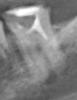

Zenden Опубликовано 18 ноября, 2010 Автор Поделиться Опубликовано 18 ноября, 2010 есть снимок зуба до лечения Ссылка на комментарий

Zenden Опубликовано 18 ноября, 2010 Поделиться Опубликовано 18 ноября, 2010 Всем добрый день, прошу советов и помощи в такой ситуации: Вчера вечером мне пломбировали каналы в зубе (нижняя семерка), после сделали контрольный снимок (показать не могу - был на приеме без флешки), врач сказал, что все хорошо. Но после этого ночью десна возле зуба распухла, а зуб сильно болел. К утру опухоль прилично спала (но не полностью), зуб болит чуть меньше, но до него все так же больно дотрагиваться даже языком! При этом до лечения зуб уже лет 10 как был без нервов, взялся его переделывать т.к. старая пломба вывалилась и у верхушки корня образовалась гранулема. До пломбировки каналов неделю ходил с временной пломбой и кажется жидким кальцием, никаких болевых ощущений не было. Вопрос: насколько подобная ситуация нормальна? Надо ли обращаться к врачу или боль постепенно пройдет? Что делать? Спасибо. Ссылка на комментарий